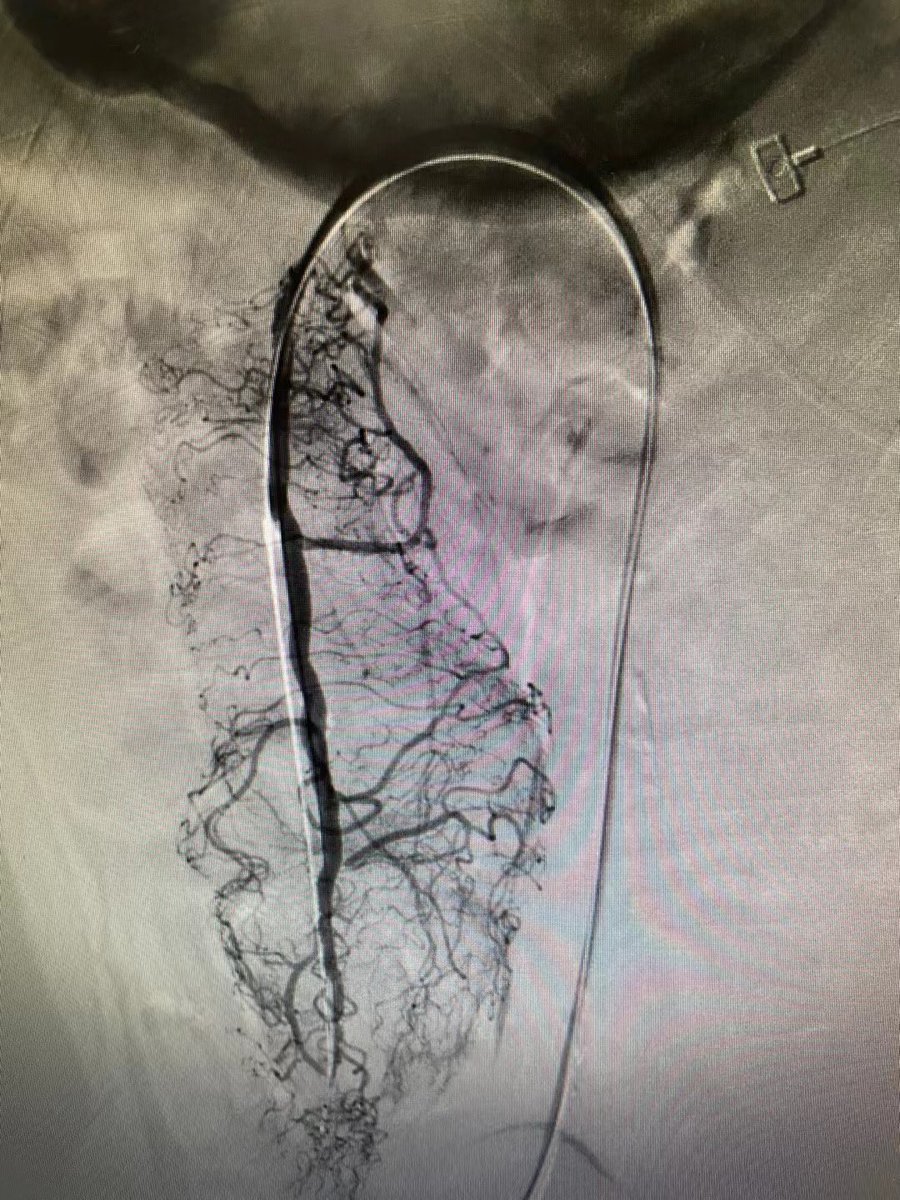

How distal can you track an AngioJet Dista device? @bostonsci @_backtable @Vascupedia_com @CLI_Global

4

3

28